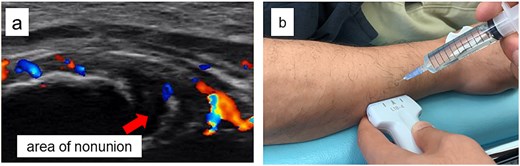

A 54-year-old man sustained a mid-diaphyseal ulnar fracture from a direct kick during karate practice. Initial conservative treatment at another hospital failed to achieve union over 12 months, and he was referred to our clinic with a diagnosis of nonunion. At presentation, he reported significant pain with a numerical rating scale (NRS) score of 6, and radiographs showed a 9 mm interfragmentary gap (Fig. 1a and b). Given his pain, we initiated proactive conservative management with prolotherapy, primarily targeting pain relief. Ultrasound revealed marked doppler signals at the nonunion site, suggesting inflammation and neovascularization. A mixture of 6 ml 50% dextrose and 4 ml 1% lidocaine (final 30% dextrose) was injected under ultrasound guidance into the neovascularized tissue and fracture gap (Fig. 2a and b). From the second session onward, bone healing had progressed to the point where the solution could no longer be injected between the bone fragments, so subsequent injections were administered around the periosteum. No restrictions were placed on weight-bearing or activity. Pain improved to NRS 4 at 2 weeks and to NRS 2 at 4 weeks, with early callus formation seen on radiographs. Prolotherapy was repeated five times at 2–3 week intervals. By 12 weeks, the patient was pain-free (NRS 0) and returned to karate. Radiographic union was confirmed at 15 weeks (Fig. 3a–d). Although initiated for pain control, prolotherapy led to relatively early bone union without surgery or complications.

Ultrasound findings and images during the procedure. (a) Ultrasound image at the start of treatment showing marked Doppler signals around the nonunion site. (b) Dextrose injection into the nonunion site under ultrasound guidance.

Radiographic findings during follow-up. (a) At 2 weeks, early callus formation is observed. (b) At 4 weeks, increased callus formation is noted. (c) At 12 weeks, near complete union is evident. (d) At 15 weeks, complete union achieved.